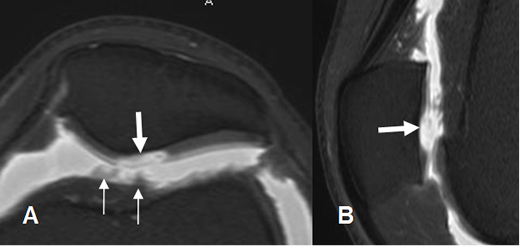

Fig 200. Osteofitos centrales.

A: Rx de túnel o proyección de Fick y B: RM coronal en T1. Presencia de osteofitos centrales,

que disminuyen la amplitud de la región intercondílea.